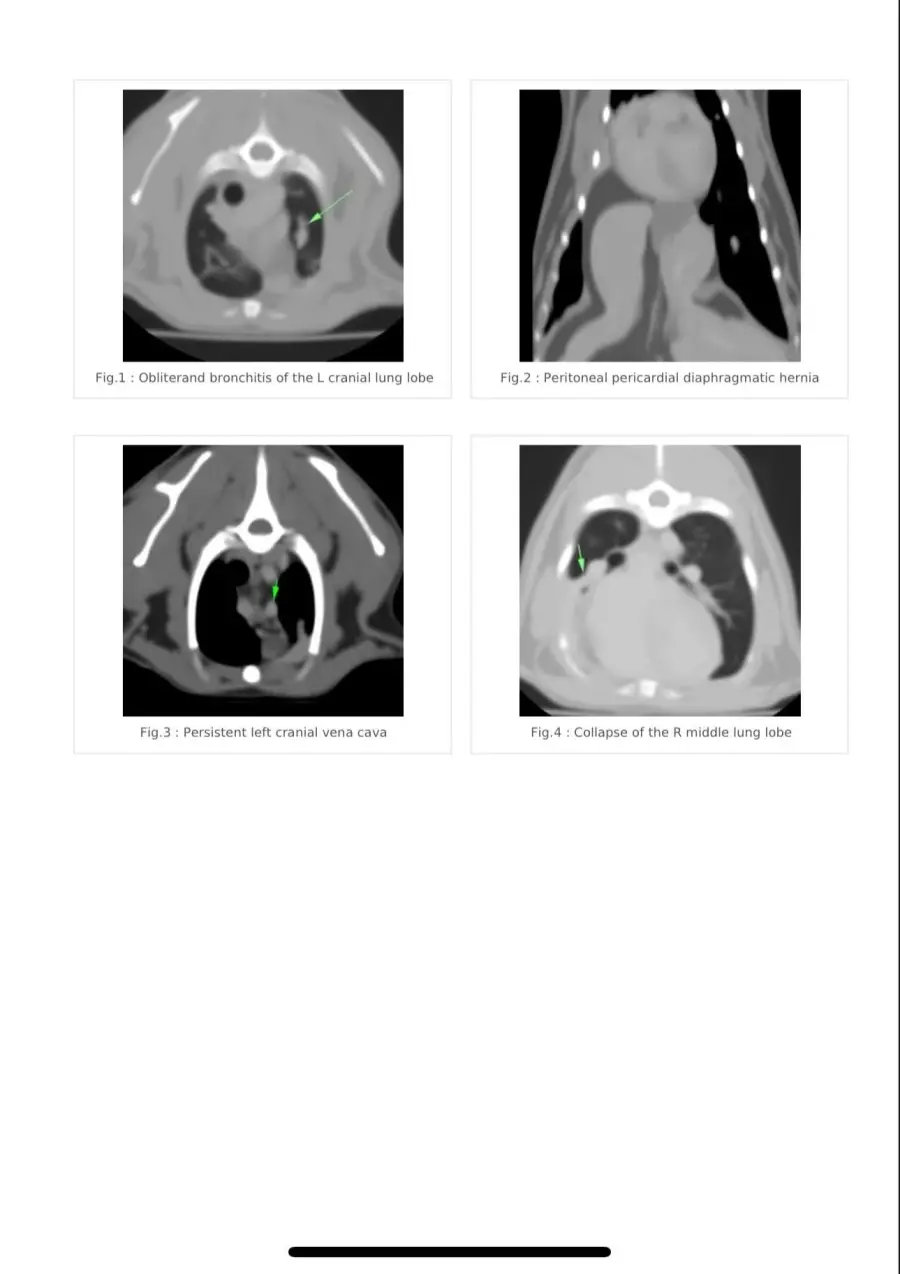

Хочу поделится своей историей покупки взрослой кошечки породы Девон рекс у заводчицы Zainaba Balabaja из питомника «Bambielf Mystery», которая в итоге оказалась больная, с врожденной деформацией диофрагмы, сросшимися органами, сжатым правым легким и еще кучей других проблем. Питомник зарегистрирован на имя её дочери Ирины Скобовы в Саласпилсе, по факту заводчица проживает и разводит котят в плявниеках. Если вкратце, весной 16го марта я приобрела у заводчицы кошечку породы Девон Рекс 4х лет, которая использовалась для разведения котят. Я и мой молодой человек созвонились с заводчицей и приехали к ней в скором времени посмотреть кошечку. В квартиру она нас не пустила, аргументируя тем что она и её муж возрастные, переболели ковидом и никого не пускают, а я наивная во все это поверила, так как это был мой первый опыт с заводчиками. Кошечку вывели на лестничную клетку в переноске, визуально она выглядела здоровой. Мы договорились об оплате наличными в размере 450 евро, о перерегистрации паспорта на меня и стерилизации через месяц в рекомендованной ей клинике, так как кошке недавно делали прививку. Договор и родословную она мне не выдала. Когда я забирала паспорт, она сказала что родословная нужна в том случае если я собираюсь водить кошку на выставки, и я решила не платить за перерегистрацию родословной на меня, так как не планировала кошку ни разводить, ни участвовать в выставках. Когда кошка начала жить у меня, спустя некоторое время у нее начали слезится глаза, заводчица уверяла что это из-за прививки. После я начала замечать что кошка часто чешется в районе подбородка и ушей, глаза все время слезились и она начала кашлять. После стерилизации кашель ухудшился, на что в клинике мне ответили что скорее всего кошка аллергик, сделали ей стероидный укол после чего симптомы прекратились на несколько недель, а потом все началось заново. На мои просьбы сделать анализы и рентген был отказ. После по совету ветов я водила кошку к вет дерматологу Евгении Кондратьевой на две консультации, были выписаны медикаменты от паразитов и курс чистки ушей, но кашель и частые чесания ушей и подбородка не прекратились. После был выписан бронхиальный ингалятор, это тоже не помогло. На мои просьбы о том, что я хотела бы сделать сразу рентген и сдать анализы был отказ, мол, надо наблюдать. В итоге в один вечер у кошки был очередной приступ кашля, который длился не минуту как обычно, а около 5-10 минут с перерывами. Я и парень повезли её в клинику Vet24, где сразу сделали рентген, взяли анализы и проверили на клещей. Какого было наше удивление когда вет принесла рентген с непонятным большим образованием давящим на органы, сказала что это не похоже на рак, но нужно делать КТ и проверить сердце. В итоге через пару дней ей сделали КТ, через месяц проверили сердце. Есть еще подозрение на проблемы с печенью, анализы на мочу показали наличие кристаллов песка. В итоге у кошки диагностировали PPDH, вкратце у кошки пока она была в эмбриональном развитии неправильно сформировалась диафрагма, образовалось отверстие и через него вышла печень и срослась с сердечной сумочкой. Органы давят на левое легкое. Правое сжатое. Сердце при этом, слава богу, пока что в порядке. Отдали мы на ветов уже больше 1000 евро, успели поменять куча кормов чтобы уменьшить симптомы аллергии и чтобы не было нагрузки на печень, переодически используем стероидный ингалятор, кошке предстоит пожизненное наблюдение у ветов, ежегодные обследования. После консультации с хирургом был сделан вывод что операцию делать смысла нет, так как с большей вероятности кошка просто умрет от потери крови. Если еще учитывать, что кошка давала потомство минимум раз в год за свои 4 года, котята давили на и так деформированные органы, а кашель заводчица просто не могла не замечать, у меня складывается подозрение что заводчица за всю жизнь кошки даже нормально ее ни разу не обследовала у вета, хотя животное ей создавало доход. Так же я нашла отзыв на sudzibas.lv за 2023 год, где мужчина приобрел двух котят у этой же заводчицы, которые оказались с клещами и хламидиозом. Жалобу я, конечно же, увидела слишком поздно. Та же схема, не пускает в квартиру посмотреть котят под предлогом ковида и уверяет что котята здоровые, а слезящиеся глазки после прививки. Сумма на ветов и обследования за пол года уже привысила 1000 евро и бог с этими деньгами на лечение, меня больше всего злит обман и абсолютное потребительское отношение к животным, которые создают тебе доход. С заводчицей после получения вет паспорта я в дальнейшем не контактировала, так как не вижу смысла выяснять отношения с человеком, который меня намеренно обманул и продал больное животное. Считаю что здесь нужно подключать соответсвующие инстанции. Скрины заключений, КТ, рентгенов прикреплю к посту. Так же сохранились скриншоты переписок с заводчицей, объявление о продаже кошки, большая часть выписок и переписок с ветами.

Прикладываю копию рентгена, результата КТ, объявление о продаже кошки, профиль заводчицы и название питомника в списке клуба Mooncat сюда в комментарии